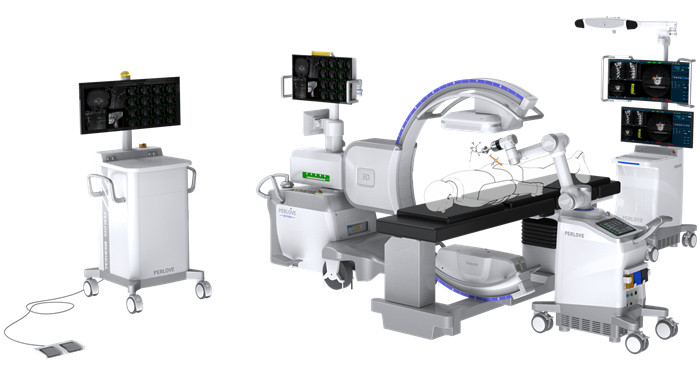

普愛醫療是術中影像領域的創新力量,其自主研發生產的三維C臂是國內目前唯一一個取得三維C三類注冊證的國產品牌。具有更大的成像視野,更加清晰的成像質量,為臨床手術的準確性和安全性提供助力。

普愛醫療三維C臂搭配骨科導航機器人,借助一體化自適應配準技術,實現自動配準和注冊,自動建立光學測位儀、患者和圖像三個坐標關聯。配準過程無需人工干預,精度不受圖像質量影響。

以椎弓根釘內固定術為例,三維C臂配合骨科導航機器人系統,可以使得治療過程可視化、立體化;協助機器人導航系統實時精準地進行手術規劃及執行,并能夠在術中即時驗證手術效果。有效地縮短手術時間,降低術中及術后并發癥的發生率。